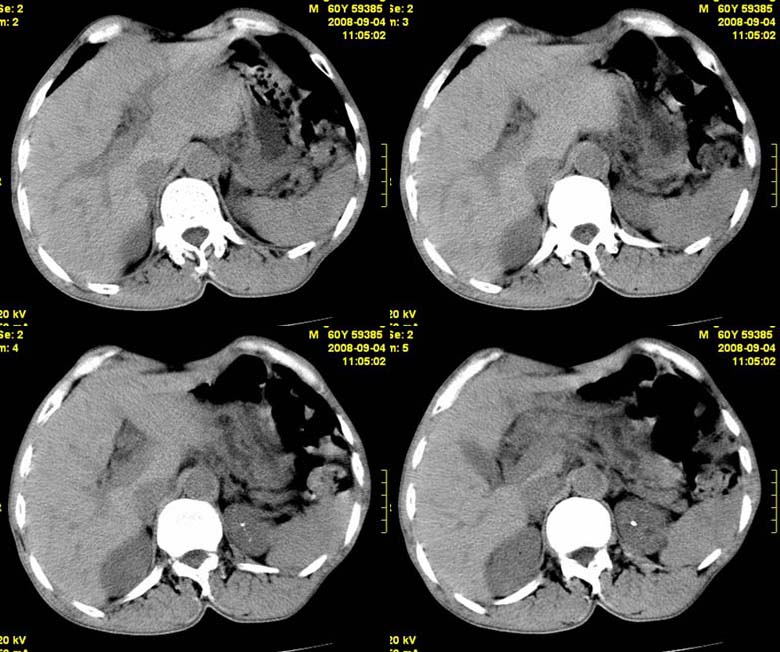

标题: CT15580:M60Y,胰腺病变,平扫+增强 [打印本页]

标题: CT15580:M60Y,胰腺病变,平扫+增强

患者,男, 60,既往有间歇腹痛病史多年,现右上腹痛,加重一月,伴右后背部疼痛,无黄疸,无发热。

考虑胰腺囊腺瘤或慢性胰腺炎

胰头区增大,胰管明显扩张,不均匀强化,且与 周围结构不清,后背疼痛,考虑为胰腺头部胰腺癌。

胰头囊腺癌

胰头囊腺癌

慢性胰腺炎

胰头囊腺癌

慢性胰腺炎并胰头癌